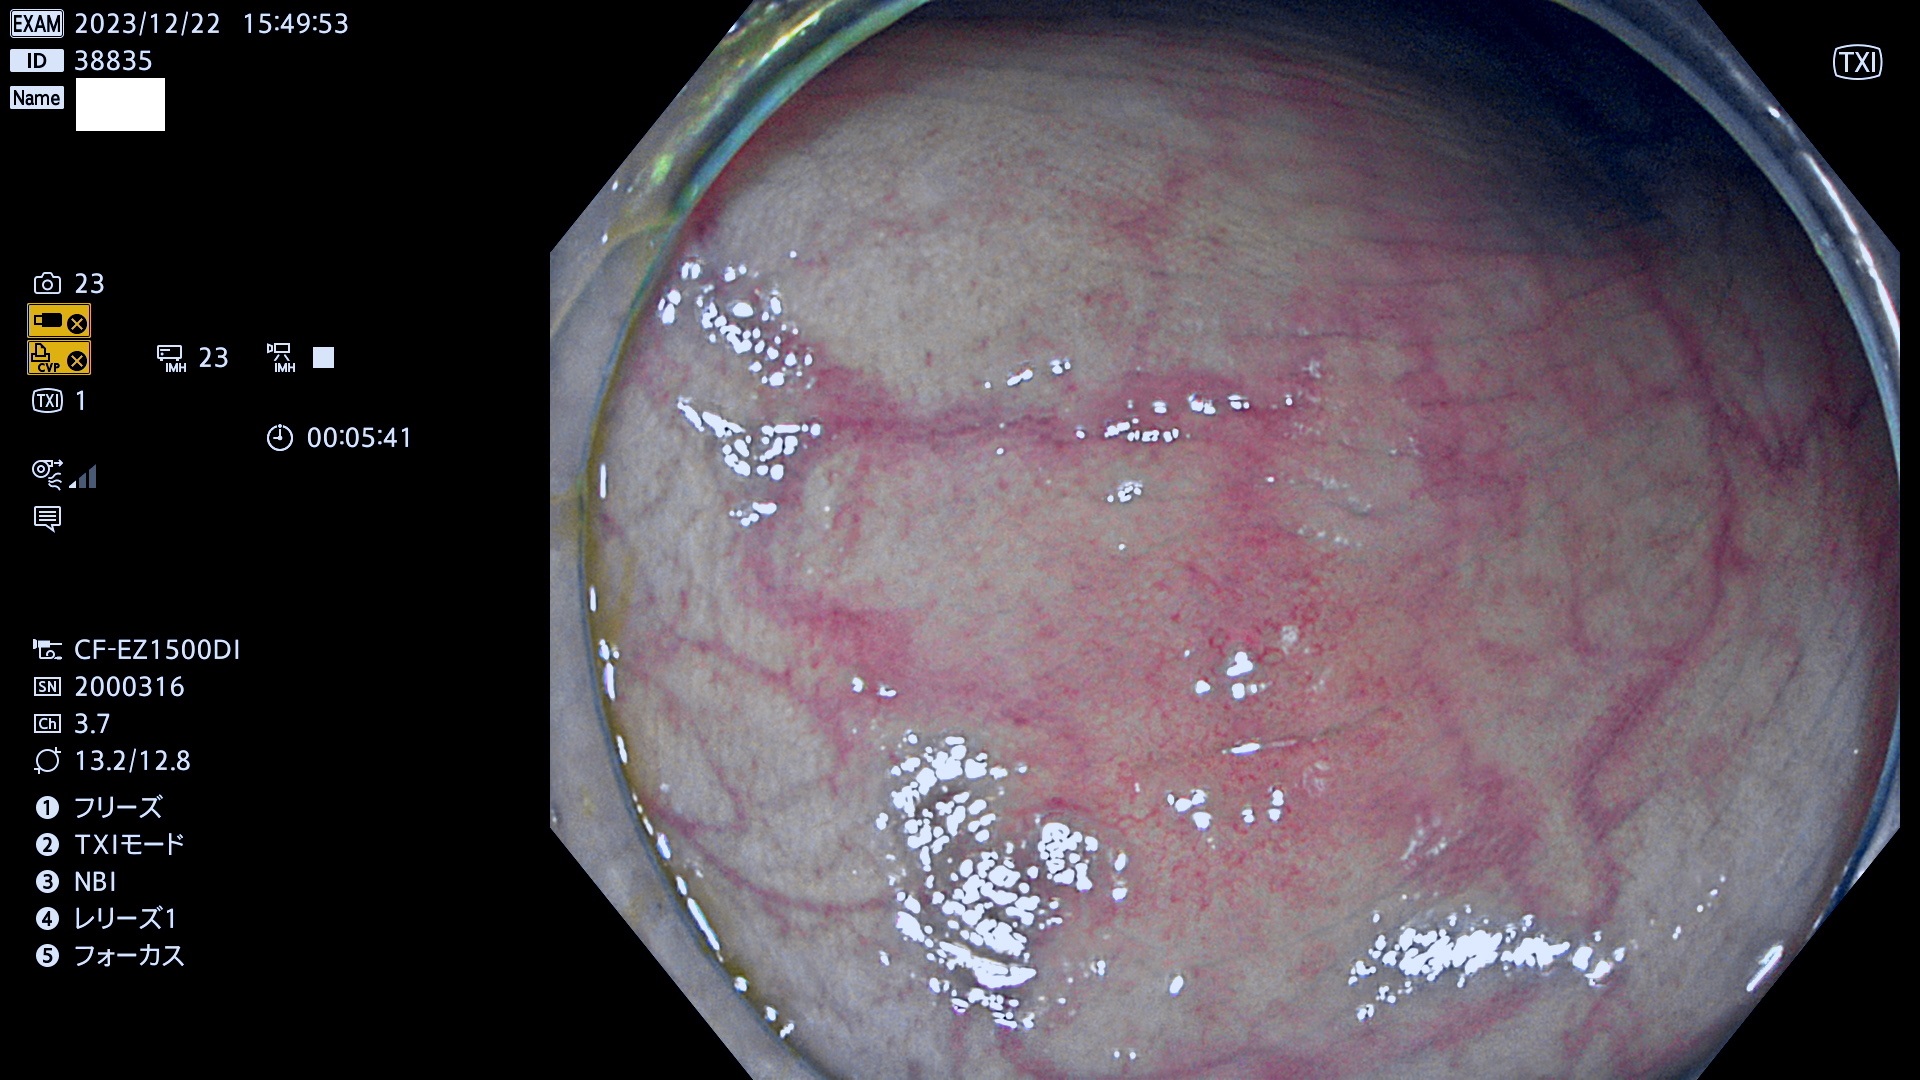

表面型腺腫(Flat Adenoma)の中で、完全に平坦な物をUb、陥凹している物をUcと呼びます。平坦隆起型(Ua)よりも、発見が難しく危険な病変です。

抽出の対象期間 2023年12月21日(木)〜12月24(日)の4日間(48件の検査)6件

当院で見つかった、炎症(ビラン)と極めて紛らわしい腺腫の例